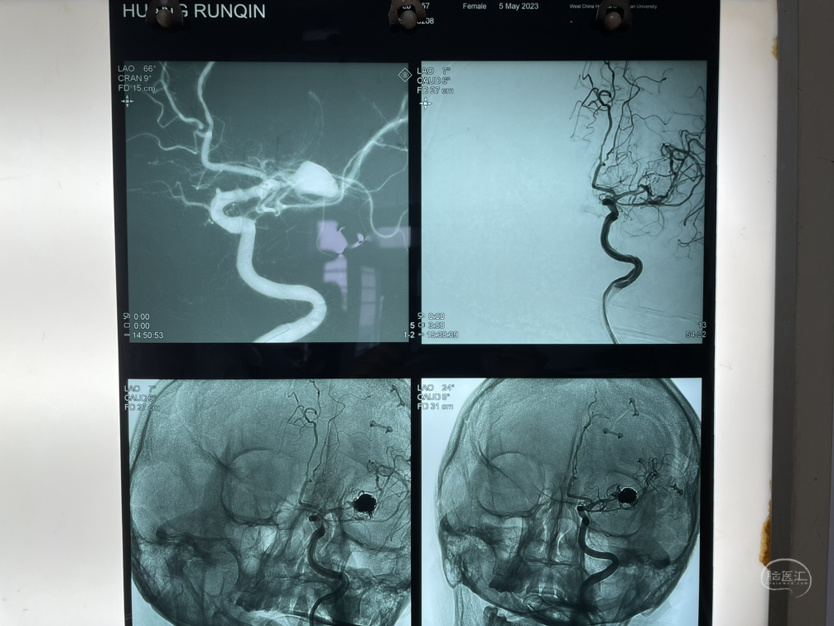

夹闭术后两个月,出院后一个月!再次出血,血肿量大,患者清醒!转上级市级医院,拟予介入栓塞后清除血肿

家属选择保守治疗,患者一直清醒!两个月前在华西行介入栓塞术,血肿吸收!